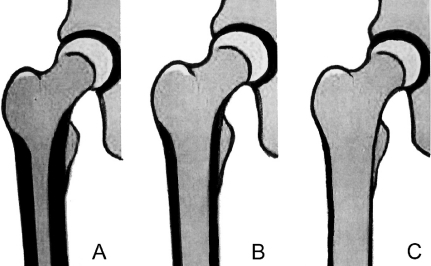

1. Single-Wedge Stems

ML(mediolateral) plane 에만 cortical engagement 를 합니다. AP 에서는 flat 합니다. Dorr B, C type 에서 시행합니다.

Dorr A 에서 사용시에 스템주변골절, 스템의 회전문제가 발생할 수 있습니다. hoop stress를 증가시키므로 대퇴 근위부 골절을 생기게 할 수 있습니다.

2. Dual Wege designs

ML, AP 모두에서 proximal femoral cortex에 engagement 합니다. Dorr A 에서 안전하게 사용할 수 있습니다.